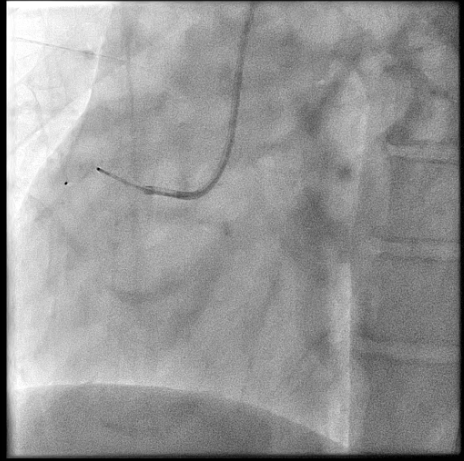

Right heart catheterization revealed a pulmonary capillary wedge pressure of 19 mmHg and mean pulmonary artery pressure of 47/27 mmHg. Pulmonary vascular resistance was 3.06 Wood units, with cardiac output of 4.9 L/min and Qp/Qs ratio of 1.24. Coronary angiography showed patent left main, LAD, and circumflex arteries. A small proximal LAD fistula and a large RCA fistula, both draining into the pulmonary artery, were identified.

The procedure was performed via left radial artery access. The right coronary fistula was engaged with a 6F AL1 guide catheter. A 5F microcatheter advanced an ASAHI Sion Black wire into the fistula tract. Given the fistula¡¯s large size and high flow, a two-device closure strategy was employed. A 7-mm AMPLATZER Vascular Plug 4 was initially deployed proximally, achieving partial flow reduction. To ensure complete occlusion, an 8-mm AMPLATZER Vascular Plug was subsequently positioned at the ostium. Final angiography confirmed marked flow reduction in the fistula while preserving native RCA flow. The small LAD fistula was left untreated due to minimal shunting. The procedure was completed without complications, and radial hemostasis was achieved.